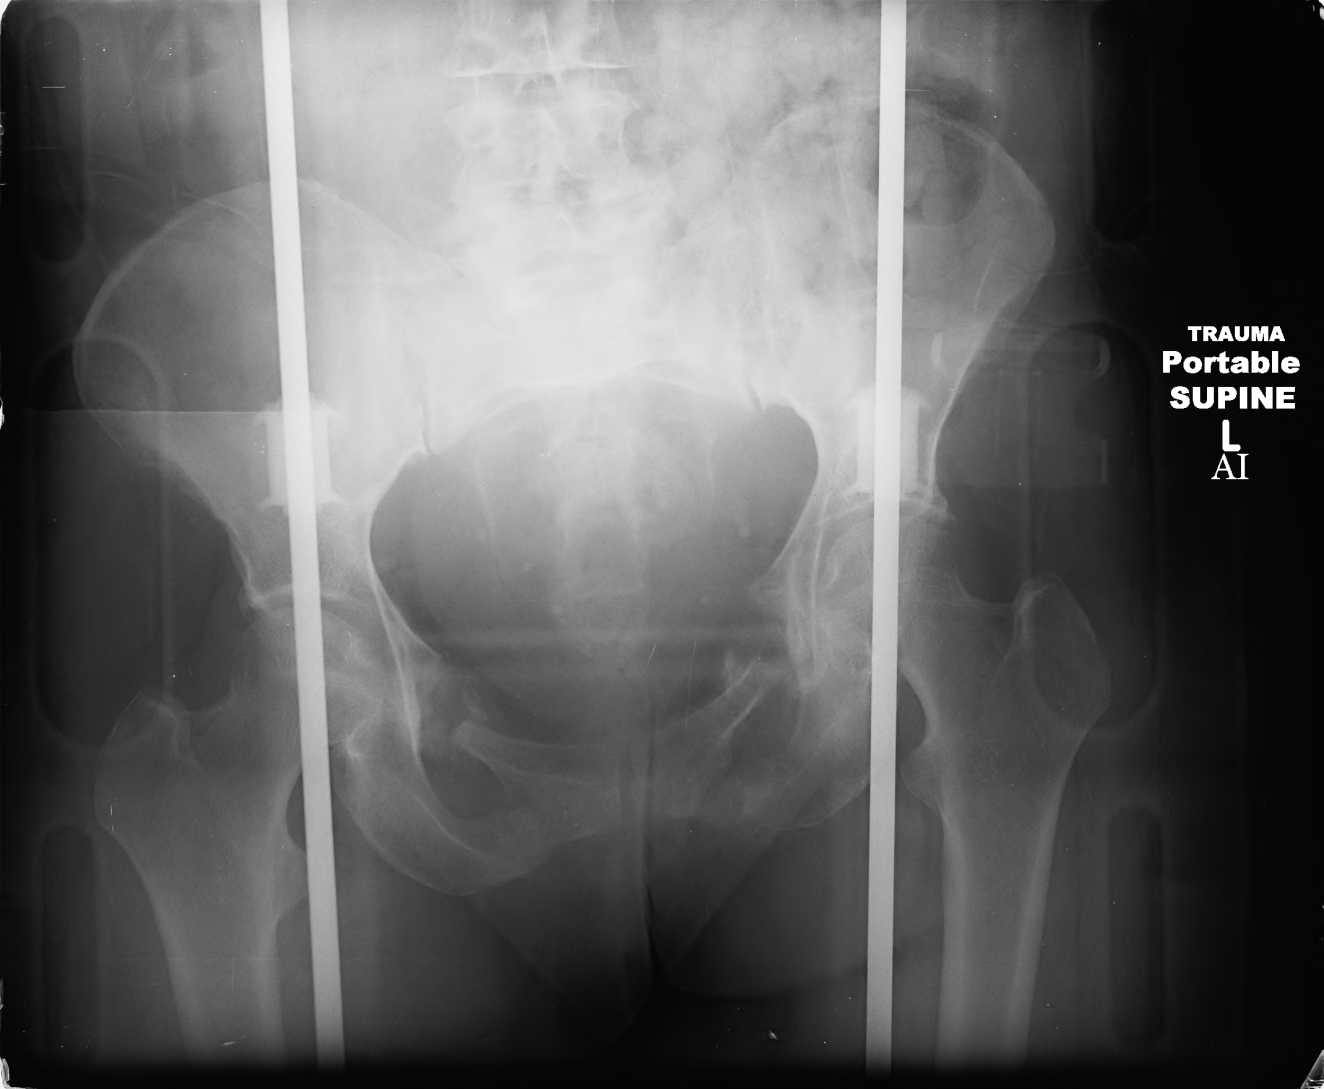

attached are images of a 59 yo female, admitted today after motor vehicle collision. Pt states her pelvis has been very painful ever since she fell on her buttocks from ground level a little over a year ago.

medical history significant for scleroderma, raynauds syndrome, and COPD. no past surgeries.

pt states she is very limited in walking ability secondary to pain. she requires a cane or a walker. friends and family do her shopping. the pain is localized primarily around left upper groin. she points to the rami region.

the question is if her medical history is contributing to the nonunions, and if anyone would consider surgical intervention, or is there some other successful intervention?